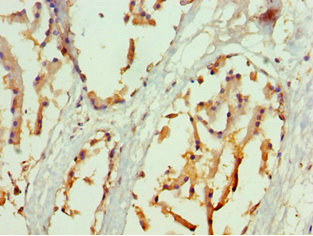

圖片:

應用范圍:ELISA, IHC

Application Recommended Dilution IHC 1:20-1:200 -